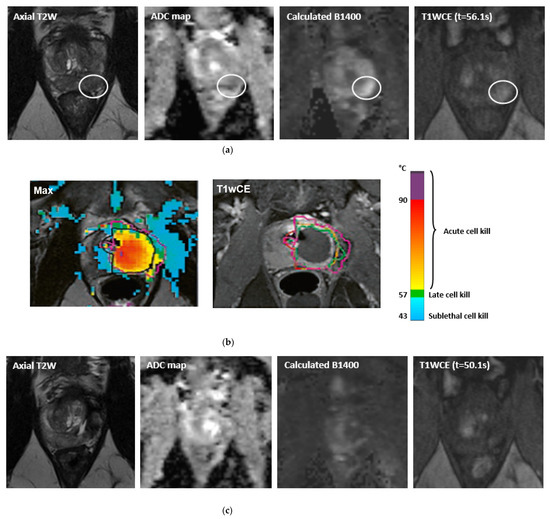

- Bomers, J.G.R.; Cornel, E.B.; Fütterer, J.J.; Jenniskens, S.F.M.; Schaafsma, H.E.; Barentsz, J.O.; Sedelaar, J.P.M.; De Kaa, C.A.H.-V.; Witjes, J.A. MRI-guided focal laser ablation for prostate cancer followed by radical prostatectomy: Correlation of treatment effects with imaging. World J. Urol. 2016, 35, 703–711. [Google Scholar] [CrossRef] [PubMed]

- Oto, A.; Sethi, I.; Karczmar, G.; McNichols, R.; Ivancevic, M.K.; Stadler, W.M.; Watson, S.; Eggener, S. MR Imaging–guided Focal Laser Ablation for Prostate Cancer: Phase I Trial. Radiology 2013, 267, 932–940. [Google Scholar] [CrossRef]

- Eggener, S.E.; Yousuf, A.; Watson, S.; Wang, S.; Oto, A. Phase II Evaluation of Magnetic Resonance Imaging Guided Focal Laser Ablation of Prostate Cancer. J. Urol. 2016, 196, 1670–1675. [Google Scholar] [CrossRef]